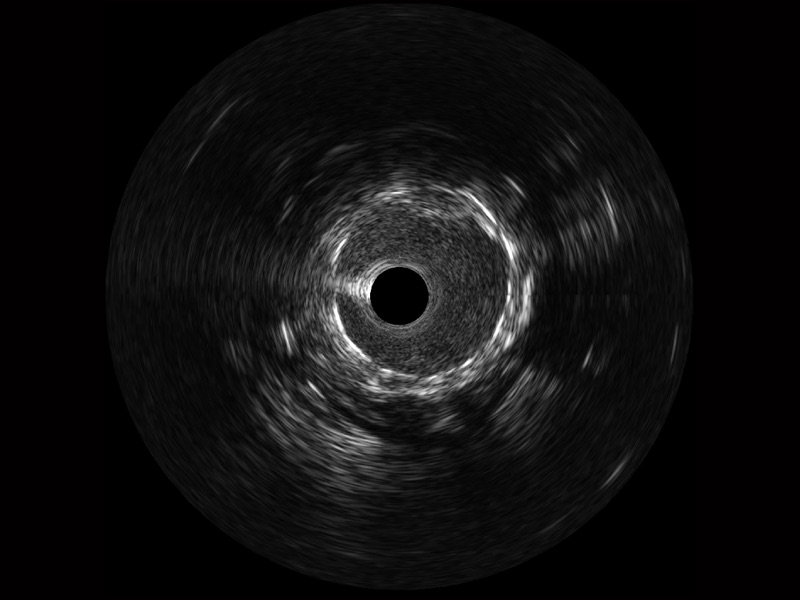

• 传统IVUS图像

对比传统IVUS导管成像,竞技宝(JJB)官方网站宽频IVUS图像的近场支架梁显影更细腻,远场中膜外血管仍清晰可辨,兼顾远中近,兼顾分辨力与穿透深度